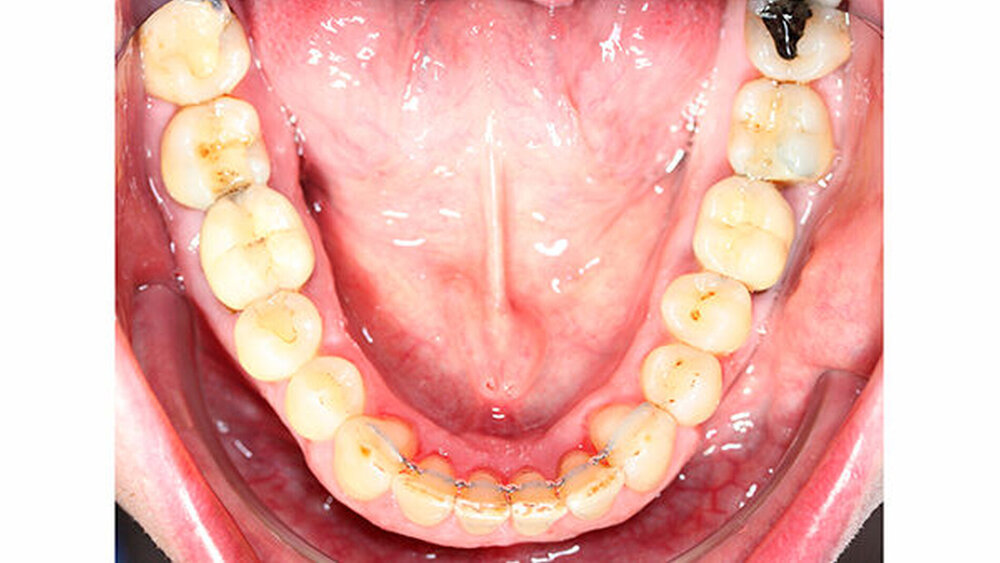

Nach erfolgter Parodontitistherapie und konservierender Versorgung stellte sich der Patient Ende 2014 erneut in unserer Praxis vor.

Die Sulkustiefen konnten auf etwas weniger als 4 mm reduziert werden, während der Blutungs- und Plaque-Index bei weniger als 15 Prozent lag. Daher wurde eine kieferorthopädische Behandlung über die nächsten zwei Jahre in Kombination mit engen zahnärztlichen Kontrollen geplant. Als Mittel der Wahl entschieden wir uns gemeinsam mit dem Patienten für das Invisalign-System, da hiermit sowohl eine Schienung als auch eine kraft-arme Bewegung der Zähne möglich sein sollte. Für den Frontzahnbereich wurden keine Attachments geplant, so dass hier eine unnötige Hebelwirkung umgangen werden konnte (Abbildung 3).